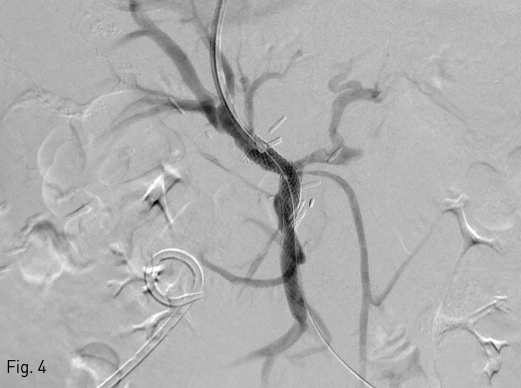

CT에서 재발암에 의한 종양혈전으로 간문맥 폐색이 있고 돼지꼬리형 카테터를 복강내 삽입하였음에도 조절되지 않는 다량의 복수가 있음(Fig. 1).

Fig 1

A contrast-enhanced CT scan shows recurrent pancreatic cancer which invaded the main portal vein (arrow), causing complete obliteration.